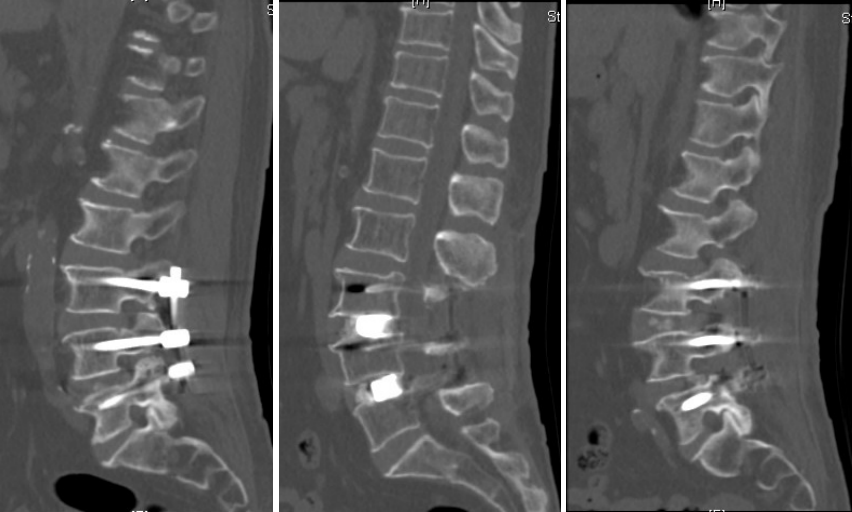

术后

术后ct